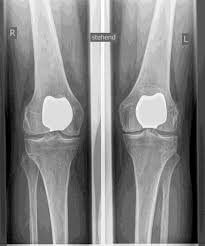

Man spricht bei künstlichen Kniegelenken von Vollprothesen und Teilprothesen. Welche Prothese für Sie in Betracht kommt, Prüfe ich sorgfältig vorher anhand der klinischen Untersuchung, sowie anhand von Röntgenbildern oder MRT-Aufnahmen.

Das künstliche Kniegelenk ersetzt die durch die Arthrose zerstörte Knorpeloberfläche. Der darunterliegende Knochen am Oberschenkel und Schienbeinkopf bleibt erhalten. Manche vergleichen ein modernes künstliches Kniegelenk mit einer

Überkronung bei einem Zahn, der genaue Begriff ist der sogenannte

bikondyläre Oberflächenersatz. Zwischen den neuen Oberflächen am Ober- und Unterschenkel befindet sich das sogenannte Inlay aus einem speziell verhärteten weißen Kunststoff, das im Röntgenbild als Abstand zwischen den Metallteilen zu erkennen ist.